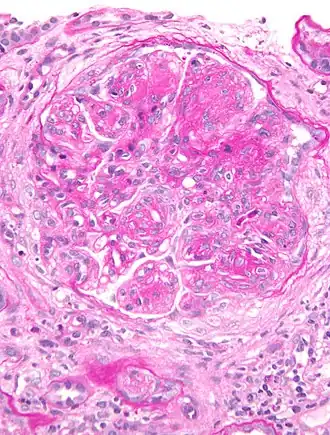

![]() Micrografía de una muestra de biopsia renal teñida con PAS que revela lesiones características de la glomerulonefritis membranoproliferativa. | ||

La glomerulonefritis membranoproliferativa (también llamada glomerulonefritis mesangiocapilar y glomerulonefritis lobular), una enfermedad renal causada por el depósito de complejos inmunes en el glomérulo, la estructura interna del riñón, ocasiona un aumento de las células glomerulares mesangiales acompañado de depósitos de anticuerpos en la membrana basal glomerular, lo que activa el sistema del complemento y daña los glomérulos.[1] La membrana basal glomerular se reconstruye sobre los depósitos inmunes y eso da lugar a una imagen peculiar en la microscopia. El daño inmunitario del glomérulo provoca alteraciones de la función del riñón.[1] Esta forma de glomerulonefritis incluye un grupo de nefropatías glomerulares poco frecuentes que comparten una lesión histológica característica y que pueden ser originadas por mecanismos patogénicos muy diversos. Más que una enfermedad como tal la glomerulonefritis membranoproliferativa debería considerarse una lesión y el hallazgo de este patrón histológico en una biopsia renal obliga a comenzar un proceso diagnóstico para establecer la etiología.[2]

La glomerulonefritis membranoproliferativa de tipo I se caracteriza por el engrosamiento difuso y global de la pared capilar e hipercelularidad endocapilar y mesangial con una acentuación de la segmentación glomerular que se denomina “lobulación”.[2] En los casos típicos se produce una duplicación de la membrana basal. Con la técnica de inmunofluorescencia se ven depósitos globales granulares o en banda de C3 e IgG. La glomerulonefritis membranoproliferativa de tipo II se conoce como “enfermedad por depósitos densos” debido a la aparición de depósitos densos intramembranosos en banda. También existe hipercelularidad lobular. La inmunofluorescencia demuestra tinción de la pared capilar para C3 lineal o en banda. La glomerulonefritis membranoproliferativa de tipo III es similar a la de tipo I pero con la presencia de depósitos subepiteliales. El patrón glomerular característico consiste en hipercelularidad mesangial, engrosamiento de la membrana basal glomerular e interposición mesangial en la pared capilar, como resultado de lo cual el glomérulo suele adoptar un aspecto lobulado. Estos cambios en la microscopia óptica explican el daño renal inicial y se producen como consecuencia del depósito de inmunoglobulinas, de factores del complemento o de ambas cosas en la pared capilar y en el mesangio.[2] Este depósito determina la llegada de células inflamatorias y el consiguiente daño causado por la inflamación (de tipo celular o proliferativo).[2] En una fase posterior de reparación se generarán una nueva matriz mesangial (expansión mesangial) y una nueva membrana glomerular que, en conjunto, ofrecerán la típica imagen de expansión mesangial y doble contorno de la membrana basal en la microscopia óptica. Las alteraciones mesangiales varían entre los pacientes pero tienden a ser uniformes entre los glomérulos de una biopsia. A veces el componente exudativo es tan importante que puede sugerir una glomerulonefritis posinfecciosa. La presencia de “trombos hialinos” en el interior de las luces capilares obliga a descartar la crioglobulinemia o el lupus eritematoso sistémico como causa de la glomerulonefritis membranoproliferativa. Los trombos hialinos no son trombos verdaderos sino agregados de inmunocomplejos que rellenan las luces capilares.[2]

La inmunofluorescencia permite distinguir si el daño renal de la enfermedad ha sido iniciado por inmunocomplejos o por desregulación de la vía alternativa del complemento. De forma genérica, en el primer caso se encuentran depósitos de inmunoglobulinas y factores del complemento de la vía clásica y en el segundo se ven depósitos exclusivos de C3. Estos hallazgos son los pilares en los que se basa la nueva clasificación.[2] En la glomerulonefritis membranoproliferativa de tipo I la alteración más llamativa en la microscopia óptica es la proliferación de células y matriz mesangial, lo que junto con el engrosamiento de la pared capilar por los depósitos subendoteliales confiere un aspecto lobulado al glomérulo. La interposición de matriz mesangial entre las células endoteliales y la membrana basal crea una imagen de desdoblamiento de la pared capilar (doble contorno). La glomerulonefritis membranoproliferativa de tipo II no se diferencia mucho de la de tipo I, salvo por un engrosamiento irregular de la pared capilar debido al depósito de un material denso. Puede haber proliferación extracapilar en ambos tipos, aunque es más frecuente en el tipo II. Con las técnicas de inmunofluorescencia la glomerulonefritis membranoproliferativa de tipo I muestra depósitos granulares de C3, junto con IgG e IgM, a lo largo de la pared capilar y del mesangio. En la de tipo II hay depósitos de C3 en el mesangio y también a lo largo de la membrana basal, lo que crea la imagen de líneas dobles semejantes a las vías del tren, pero no hay depósitos de inmunoglobulinas. La microscopia electrónica muestra con mayor claridad los depósitos subendoteliales en la enfermedad de tipo I y en la de tipo II permite establecer el diagnóstico porque revela el importante nivel de engrosamiento de la membrana basal debido a que en su parte central se localiza un material electrodenso que reemplaza y ensancha la lámina densa.[5][6]